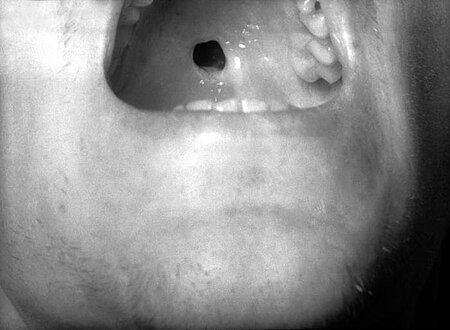

High arched palate, oral fissures, and runny and congested nose

Late onset features include deformity of the nose, lower legs, forehead, collar bone, jaw, and cheek bone.[1] Some of these bone defects can be detected early.[16] There may be a perforated or high arched palate, and recurrent joint disease.[1][4] Other late signs include scarred skin, intellectual disability, hydrocephalus, and juvenile general paresis.[1] Eighth nerve palsy, interstitial keratitis and small notched teeth may appear individually or together; known as Hutchinson triad.[1][18]

Perforation of palate

Perforated hard palate